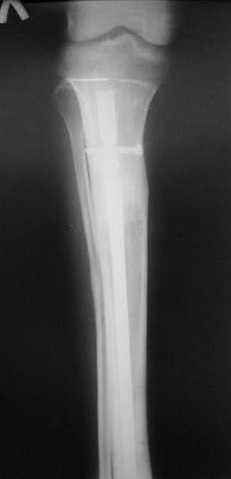

Пациент 19 лет, производственная травма, придавлен тяжелой плитой. Политравма (ISS 21).

1 - рентгенограмма (прошу прощения за качество) при поступлении;